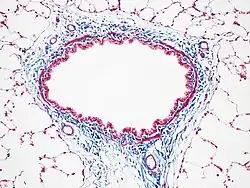

Masson's trichrome stain

Masson's trichrome stain of rat airway. Connective tissue is stained blue, nuclei are stained dark red/purple, and cytoplasm is stained red/pink.